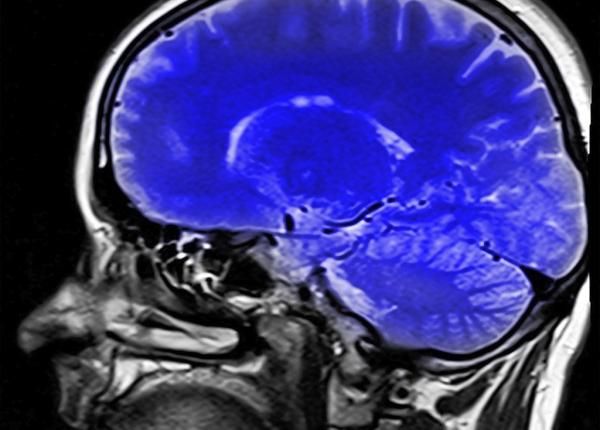

Conferința Națională Alzheimer, sănătatea mintală – prioritate pe agenda publică!

Conferința Națională Alzheimer, Ediția a 9-a, Actualități în domeniul demențelor, organizată de Colegiul Medicilor din Municipiul București în parteneriat cu Societatea Româ...